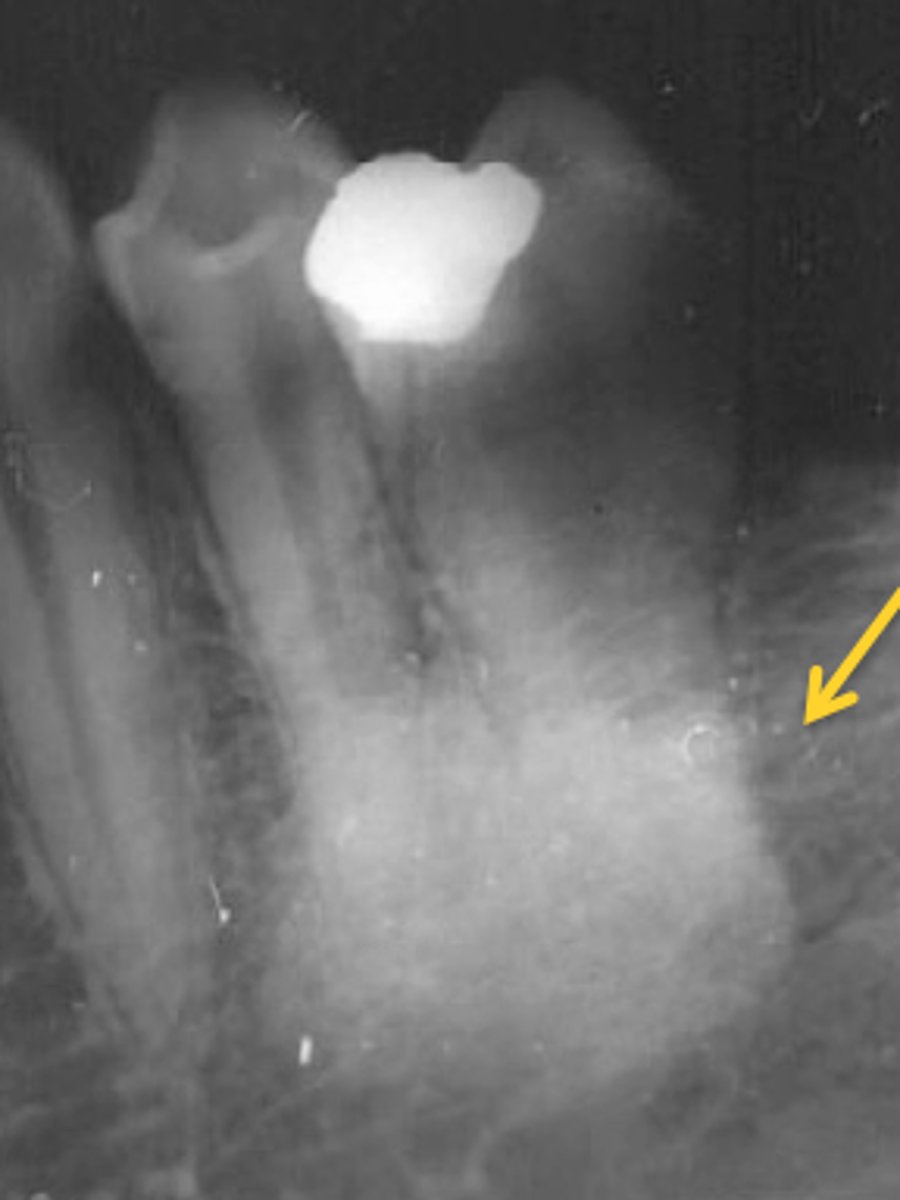

periapical

radiographic image showing the crown, root tip, & surrounding structures

periapical radiographs used to detect:

any abnormalities of the root structure & surrounding bone structure

the most common radiographic exposure used to evaluate a dental implant on an adult is: